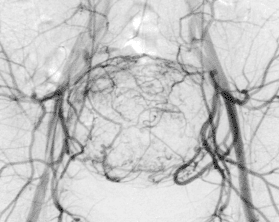

Abbildung:

Abbildung A zeigt eine MR Angiographie der Becken-Bein-Arterien bei Patient:innen mit Verschluss der Aorta infrarenalis sowie der Beckenarterien beidseits. Es besteht ein Zustand nach Anlage eines axillofemoralen Bypass sowie Anlage einer Links-Rechts-Umleitung. Auch die Oberschenkelarterien sind beidseits verschlossen.

Abbildung B zeigt eine MR Angiographie der Becken-Bein-Arterien bei einem Patient:innen mit Zustand nach Anlage eines femoropoplitealen Bypasses rechts. Darüberhinaus besteht ein Aneurysma der linken A. poplitea.